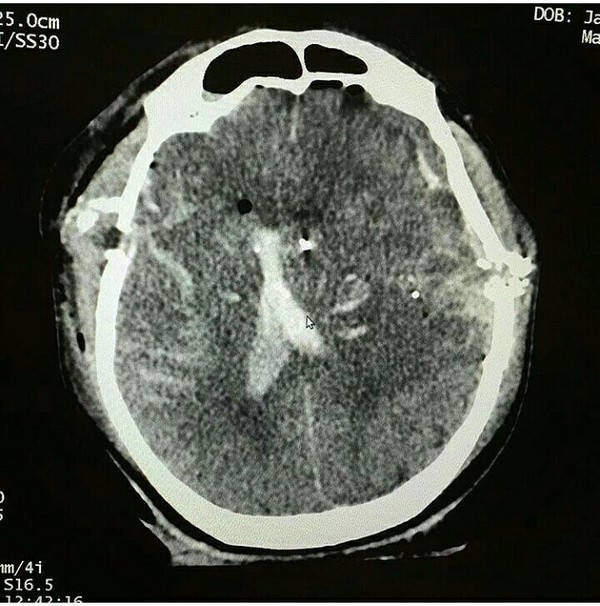

Пистолетная пуля 38 калибра прошла сквозь черепную коробку, не задев жизненно важных центров. Опасность при пулевых ранениях представляет не столько раневой канал, сколь контузия окружающих тканей. Данному пациенту повезло, пуля прошла на высокой скорости и не "виляла". Таким образом его шансы на выживание весьма высоки.